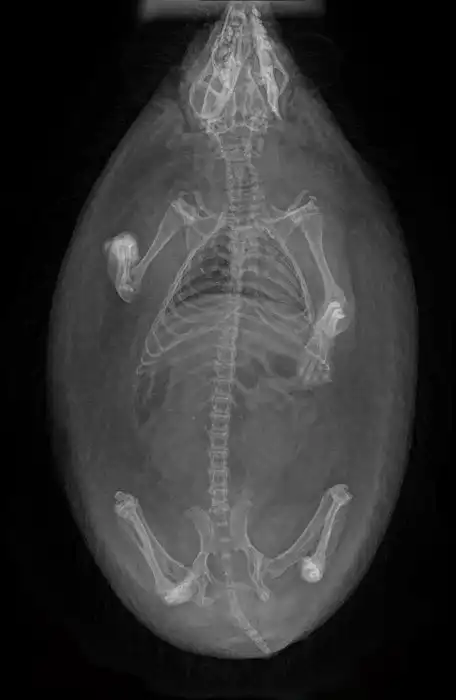

5. Рентген беременной собаки